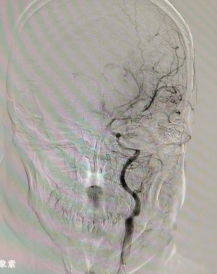

烟雾病是一种罕见的慢性闭塞性脑血管疾病,其病因目前尚不明确。该疾病的主要表现为颈内动脉(ICA)末端进行性闭塞伴颅底异常烟雾状血管网形成,因其在脑血管造影上形似“烟雾”而得名,多发于青壮年,具有极大的危害性。多数患者因出现临床症状而就医,烟雾病的临床表现主要包括脑梗死、脑出血、癫痫发作、神经功能障碍等。检查方式主要有磁共振、CTA等,而最佳的检查方法为DSA脑血管造影术。

此次的女性患者李某、尹某以及男性患者李某,均在1月前因脑梗塞或蛛网膜下腔出血而进行了DSA检查,确诊为烟雾病。他们通过多方了解,找到了东方总院神经外科的张德辉院长。张院长凭借丰富的搭桥手术经验,详细解释了烟雾病的病因、临床表现、鉴别方式、治疗方式,并介绍了与鼓楼医院神经外科的合作平台及杨咏波教授在烟雾病搭桥手术上的高超技术和丰富经验。家属们听后毫不犹豫地选择在东方总院神经外科进行搭桥手术。经过手术,三位患者恢复良好,无并发症,术后第二天便开始下床活动,并在一周后康复出院。